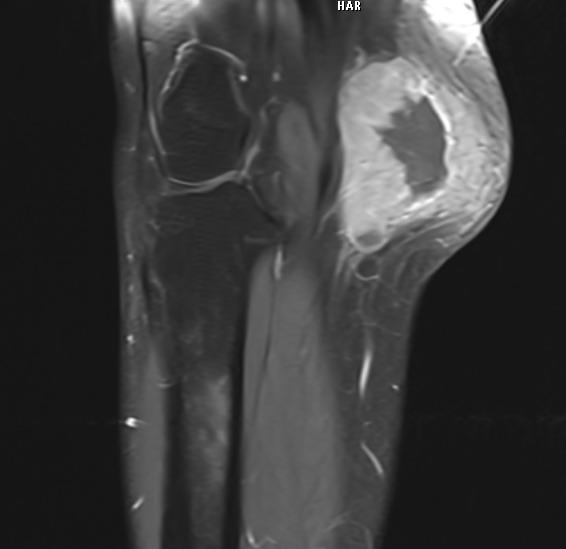

Muscle Cancer